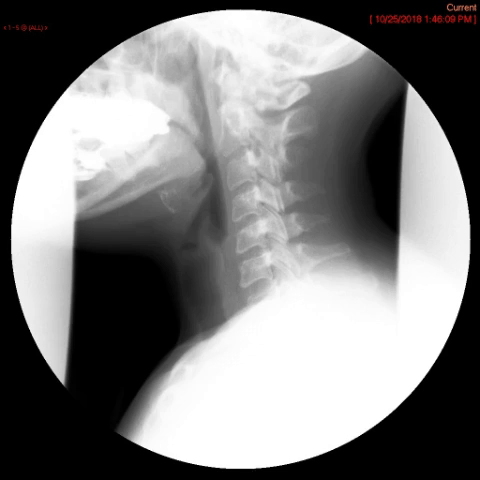

- Method—Cervical:

- Start with the patient in the upright lateral position.

- Ensure the fluoro machine is set to 4 images per second (rapid sequence).

- Explain to the patient that you are going to have them take a "comfortable mouthful" of barium and that they will need to hold it in their mouths until you count to 3.

- Make sure they understand that they are not to swallow until the count of 3.

- Once the patient has taken the "comfortable mouthful" of barium, center the fluoroscope on the cervical esophagus.

- Once the fluoroscope is properly positioned, begin counting. On the count of 2, begin taking rapid sequence images of the contrast material bolus as it moves through the cervical esophagus

(key image 1)

- Take the fluoroscope off rapid sequence.

- With the patient in the lateral position, obtain a spot film of the pharynx and cervical esophagus while they phonate the letter "e"

(key image 2).

- Cervical images are obtained in the lateral and AP projections as the patient swallows thick barium.

- Cervical image are obtained using rapid sequence fluoroscopic spot films at a rate of 4 frames per second.

- To time this appropriately, you will count to 3. You will begin to take images on 2, the patient will swallow on 3.